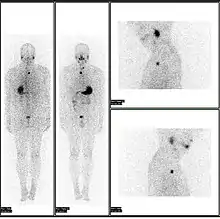

A nuclear medicine parathyroid scan demonstrates a parathyroid adenoma adjacent to the left inferior pole of the thyroid gland. The above study was performed with Technetium-Sestamibi (1st column) and iodine-123 (2nd column) simultaneous imaging and the subtraction technique (3rd column).